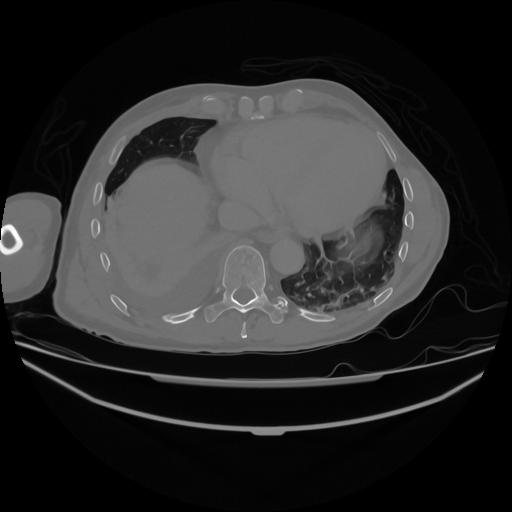

5 CUERPO,CE,Vol,1.0,CUERPO,,